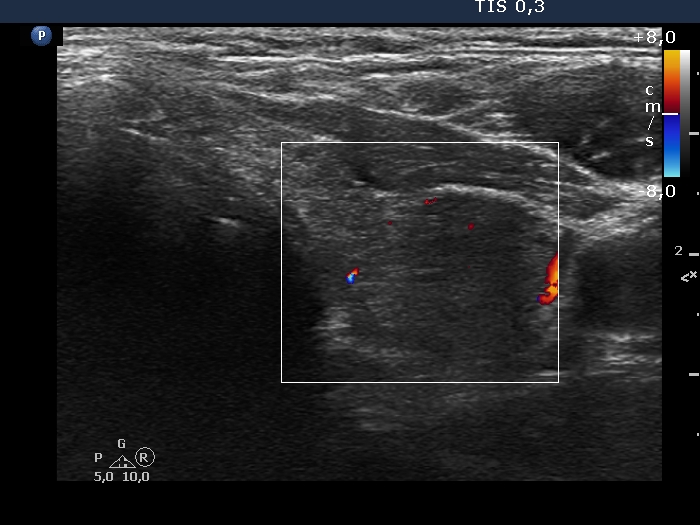

100 consecutive cases of papillary cancer - case 084 (ultrasonographic picture 8)

Left lobe, transverse scan, color Doppler mode. The lesion is almost avascular.